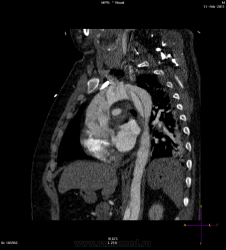

21.02.2011 МСКТ-органов грудной полости.

Пациент 44 года, поступил экстренно в тяжелом состоянии, при осмотре зрачки разные D>S.

Расслаивающая аневризма. Тип А.

Насколько видно на этих сканах расслоение пошло на левую общую сонную и левую подключичку выше за контур сканирования. Справа к сожалению четко не вижу.

К сожелению у нас технические проблемы с гентри, поэтому исследование не проводилось как ангиографию, но тем не менее, аппарат выдал ошибку, поэтому брюшной отдел аорты пришлось досматривать в отсроченную фазу, но там видно было переход на подвздошные. На втором скане видно расширение плече-головного ствола, вообщем переход на сосуды шеи есть. Через 40  минут после исследования была констатация биологической смерти.

Состояние острое, с учетом распространения(тип А), конечное может быть, что угодно, первоначально точно наличие инсульта правой гемисферы мозга. О заключении патологоанатомов не могу сказать окончательно.